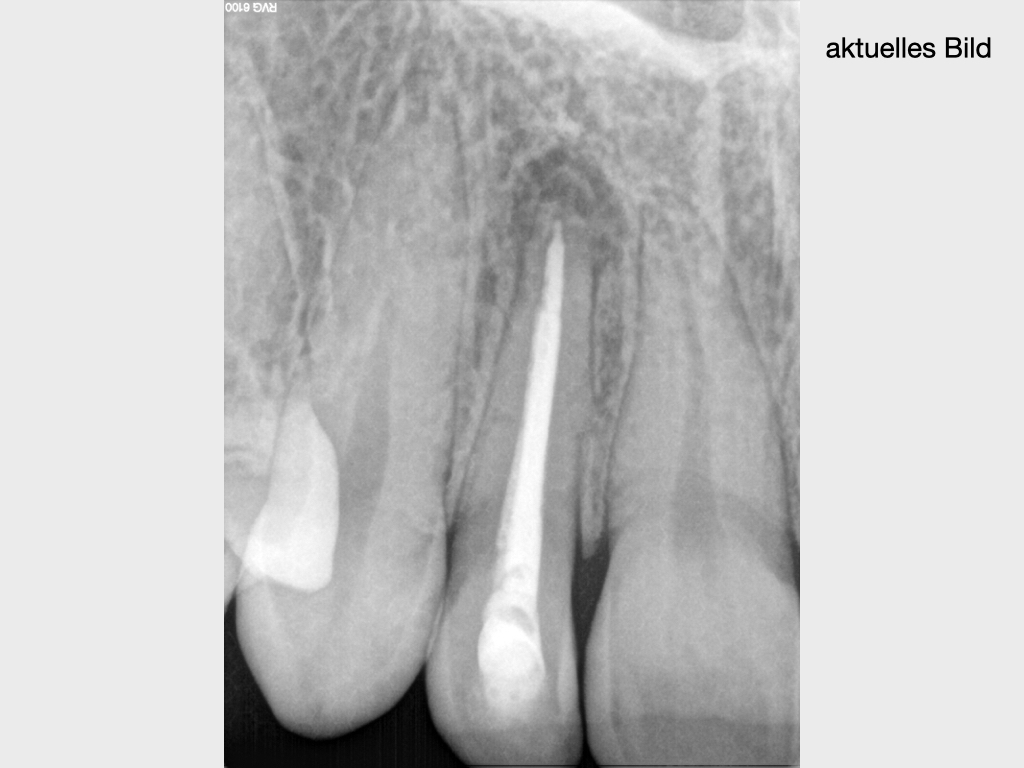

Die Revision der Revision…